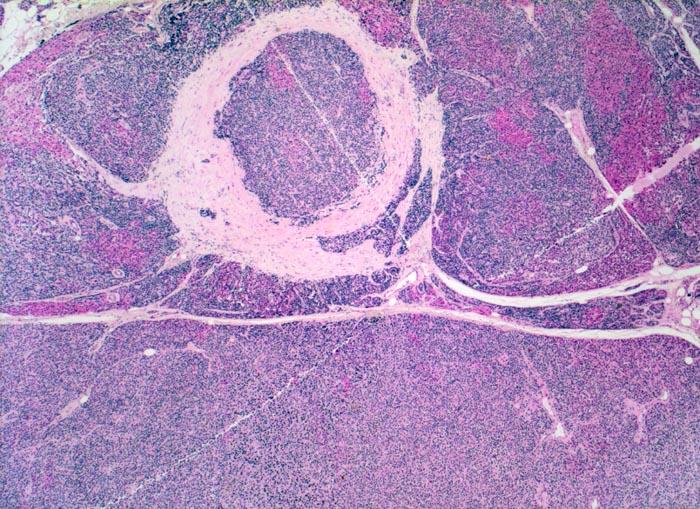

noduläre Nebenschilddrüsenhyperplasie

Das Gewebe ist knotig strukturiert: die Knoten sind teils rötlich (onkozytäre Zellen), teils bläulich gefärbt. Im hyperplastischen Parenchym ist kein Fettgewebe erkennbar.

Bei der nodulären Hyperplasie sind alle Nebenschilddrüsen knotig vergrössert. Im Gegensatz zur Hyperplasie manifestieren sich Adenome der Nebenschilddrüse meistens als solitäre bekapselte Knoten. Im Randbereich von Adenomen findet man in 50% der Fälle nicht neoplastisches supprimiertes (atrophes) Nebenschilddrüsengewebe mit reichlich Fettzellen und verkleinerten Hauptzellen.